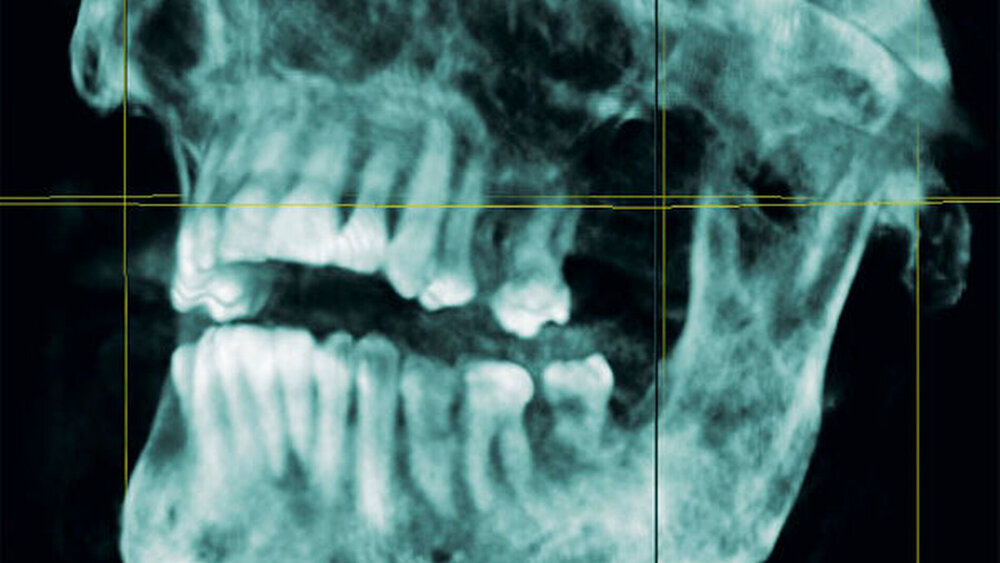

Zum Ausschluss einer Mittelgesichtsfraktur bei palpatorischem Weichteilemphysem erfolgte zur weiteren Diagnostik eine DVT-Aufnahme. Es zeigten sich keine Frakturen im Bereich des Mittelgesichts oder der Kiefer. Jedoch kam in der DVT-Bildgebung sowie in der OPT-Optik ein massives Weichgewebeemphysem zur Darstellung (Abbildungen 2 bis 5).

Weiterhin wird deutlich, dass bei in aller Regel doch sehr eingeschränkter Beurteilbarkeit von Weichgewebe im DVT in diesem speziellen Fall eine weiterführende Diagnostik und Therapie eingeleitet werden konnte.

Das Emphysem war initial im DVT so eindrucksvoll sichtbar, dass es trotz fehlender klinischer Symptomatik im Thoraxbereich, schwieriger Anamnese und blander zweidimensionaler Bildgebung der Lunge (RÖ-Thorax) der Faktor für eine weitere dreidimensionale Bildgebung (CT-Thorax) war, die letztendlich die Verdachtsdiagnose sicherte.

Zur Frakturdiagnostik im Mittelgesichtsbereich eignet sich das DVT sehr gut, außerdem ist die freie Luft des Emphysems im undifferenzierten Weichgewebe gut darstellbar.

Mittels der digitalen Volumentomografie können Weichteile schlecht bis gar nicht beurteilt werden, Lufteinschlüsse im Weichgewebe hingegen können gut dargestellt werden.